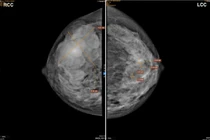

vusa1.jpg

Phẫu thuật lấy và tạo hình tuyến vú sa trễ - Ảnh BVCC

Bệnh nhân Vũ T T (52 tuổi, tỉnh Quảng Ninh) có nhiều khối u vú 2 bên nhiều năm nay nhưng gần đây vú trái đau tức nhiều, hai bên tuyến vú phì đại, sa trễ, tức nặng. Kết quả siêu âm vú trái có hình ảnh nang tuyến vú trái (BIRADS 4), nhân tuyến vú 2 bên (BIRADS 3).

Kết quả chọc hút tế bào (FNA) và xét nghiệm mô bệnh học sau mổ cho thấy bệnh nhân có các khối u và nang tuyến vú lành tính. Các bác sĩ đã chẩn đoán: Đa nhân, nang tuyến vú 2 bên/ Phì đại, sa trễ độ 3 vú 2 bên, chỉ định phẫu thuật cắt phần tuyến vú chứa u 2 bên và thu nhỏ tuyến vú phì đại, sa trễ cho người bệnh.